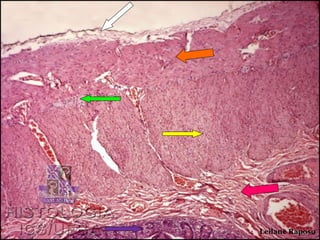

Monitoria de Histologia II

•   Identifique a camada apontada pela seta branca.

•   Qual a estrutura apontada pela seta verde?

•   Qual a camada apontada pela seta laranja?

•   Qual a camada apontada pela seta amarela?

•   Qual a camada apontada pela seta rosa?

•   Qual a camada apontada pela seta roxa?